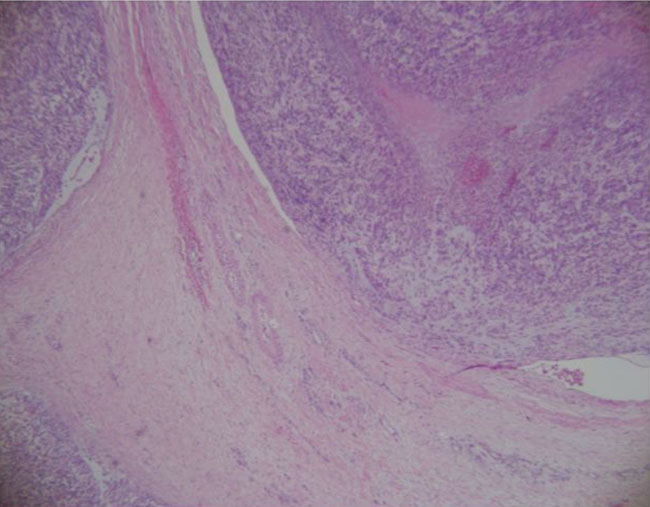

The patient underwent right radical inguinal orchiectomy with excision of the spermatic cord. A paratesticular mass grossly measuring 9.7 × 7 × 6.5 cm was excised and sent for pathologic examination. Microscopy revealed a malignant spindle cell neoplasm consistent with leiomyosarcoma associated with areas of hypercellularity measuring 24 mitoses per 10 high-power fields (0.1735 mm2) and positive surgical margins (Figure 2). There was evidence of lymphovascular involvement of the testicular vein without invasion of the vas deferens or the spermatic cord stroma (Figure 3 and Figure 4). Immunohistochemistry was diffusely reactive for calponin, caldesmon, desmin, and smooth muscle actin immunostains. The final pathologic stage classification was pT2 (pTNM; American Joint Committee on Cancer, 8th edition). Staging CT scans of the chest, abdomen, and pelvis were negative for metastatic disease. Following multidisciplinary discussion, adjuvant radiotherapy was offered but deferred after careful consideration of this patient’s case. Scrotal immobilization during radiotherapy is challenging and limits the delivery of a targeted, reproducible radiotherapy dose. Furthermore, an extensive postoperative radiotherapy field would be required. The patient remains disease-free at one month of follow-up after surgery, with plans for continued surveillance.

Figure 2: Hematoxylin and eosin (H&E) stain, 200× demonstrating fascicles of spindle cells, some with atypia.

Figure 3: H&E stain, 400× demonstrating leiomyosarcoma attached to the wall of the spermatic vein.